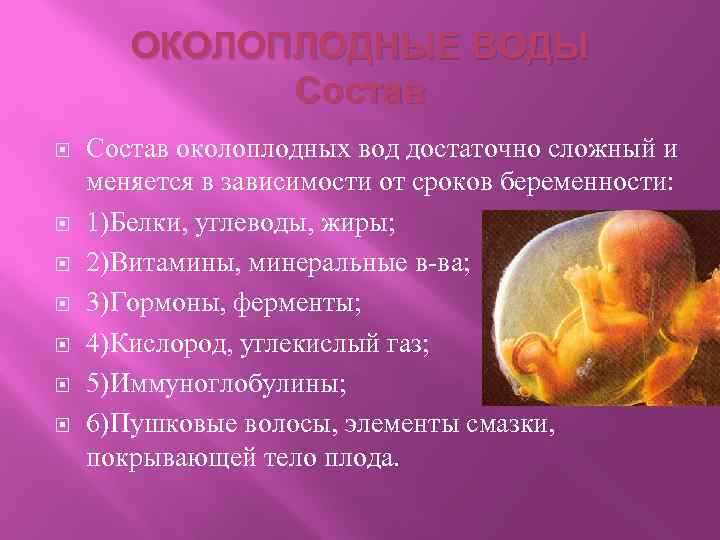

Многоводие при беременности: симптомы и лечение